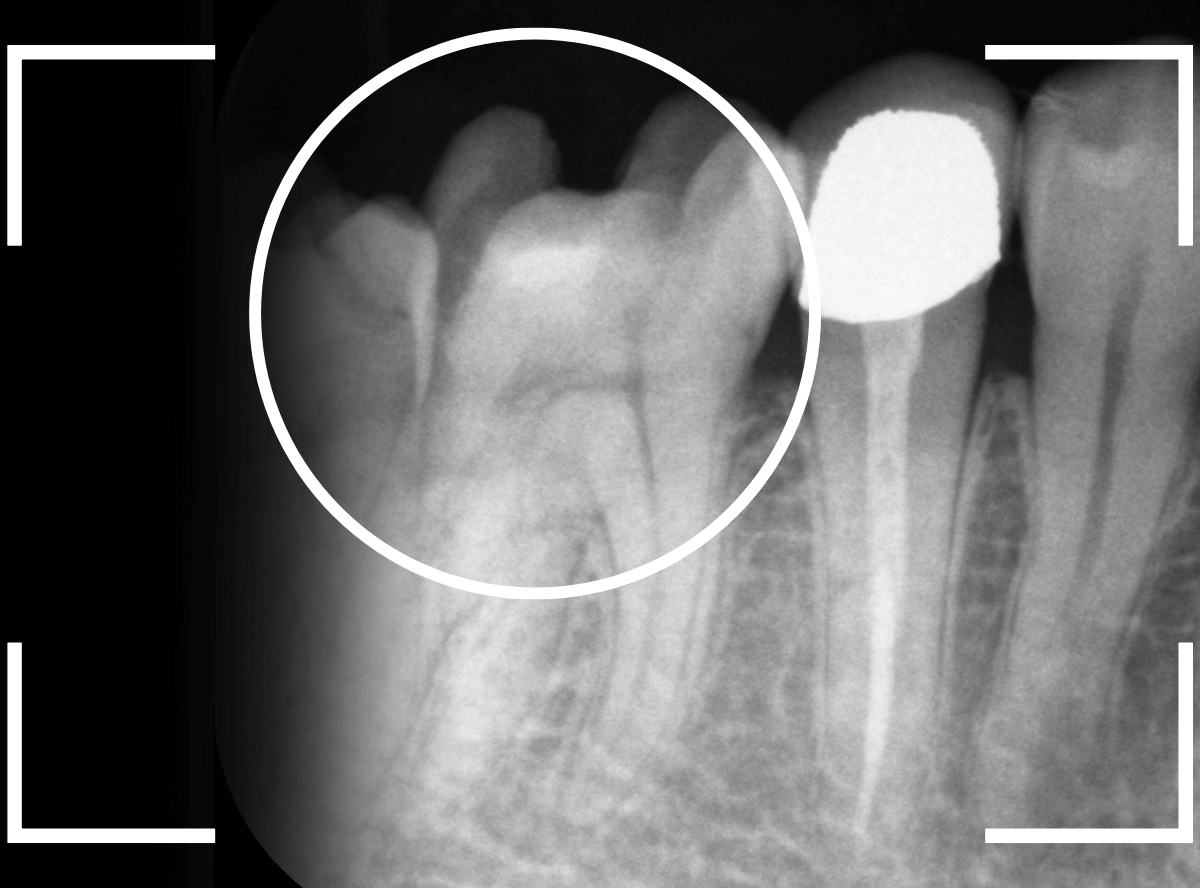

Case.18 虫歯なのは間違いないが、境界がはっきりしない

「つめものが外れて、噛むと痛い」という訴えで来院された患者さんさんです。

一見で、表面が虫歯になっているのと、レジンが劣化しているのがわかります。

レントゲン写真で確認します。

〇部が当該の歯です。

症状もあるので、虫歯が深そうですが、全体がもやっとして、どこからどこまで虫歯なのかはっきりわかりません。

まれに、こんな時もあります。

レジンを外し、虫歯の処置を進めます。

慎重に虫歯を除去し、一安心か、という寸前で(〇部、小さく出血しているところ)露髄してきました。

神経を除去しないとダメかもしれません。。。

神経を保護するお薬をつめて、経過観察します。

痛みが出ませんように。。。